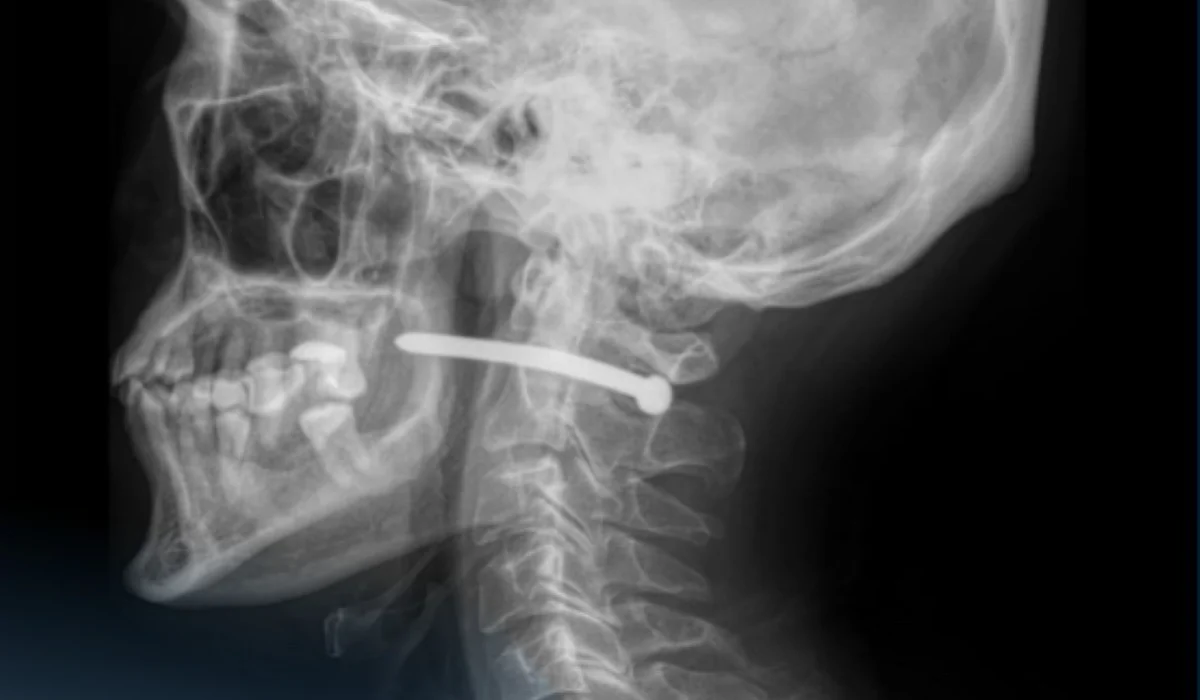

Көп бейінді қалалық жедел медициналық жәрдем ауруханасына 51 жасар ер адам құлақ маңындағы жарамен көмекке жүгінген. Ол жөндеу жұмыстары кезінде шегеге арналған пневматикалық құралдың шегесінен жарақат алған.

«Рентген-зерттеуден кейін шегенің омыртқаның мойын бөлігінен өткені анықталды. Ер адамның көрер жарығы бар екен – өміріне маңызды органдары зақым алған жоқ», - деп жазды аурухананың баспасөз қызметі.

Жақсүйек-бет хирургтары жарадан шегені алып, қарап, жараны өңдеді. Жара тігіліп, стерильді таңғыш салынғаннан кейін науқасқа ұсыныстар беріліп, үйіне жіберілді.

«Мойын тұзына жарақат алу өте қауіпті – мойынның маңайынан үлкен тамырлар, нервтер, тыныс алу жолдары және жұлын өтеді. Тіпті кішкене ғана зақым алудың салдары ауыр болуы мүмкін», - деп ескертті дәрігерлер.